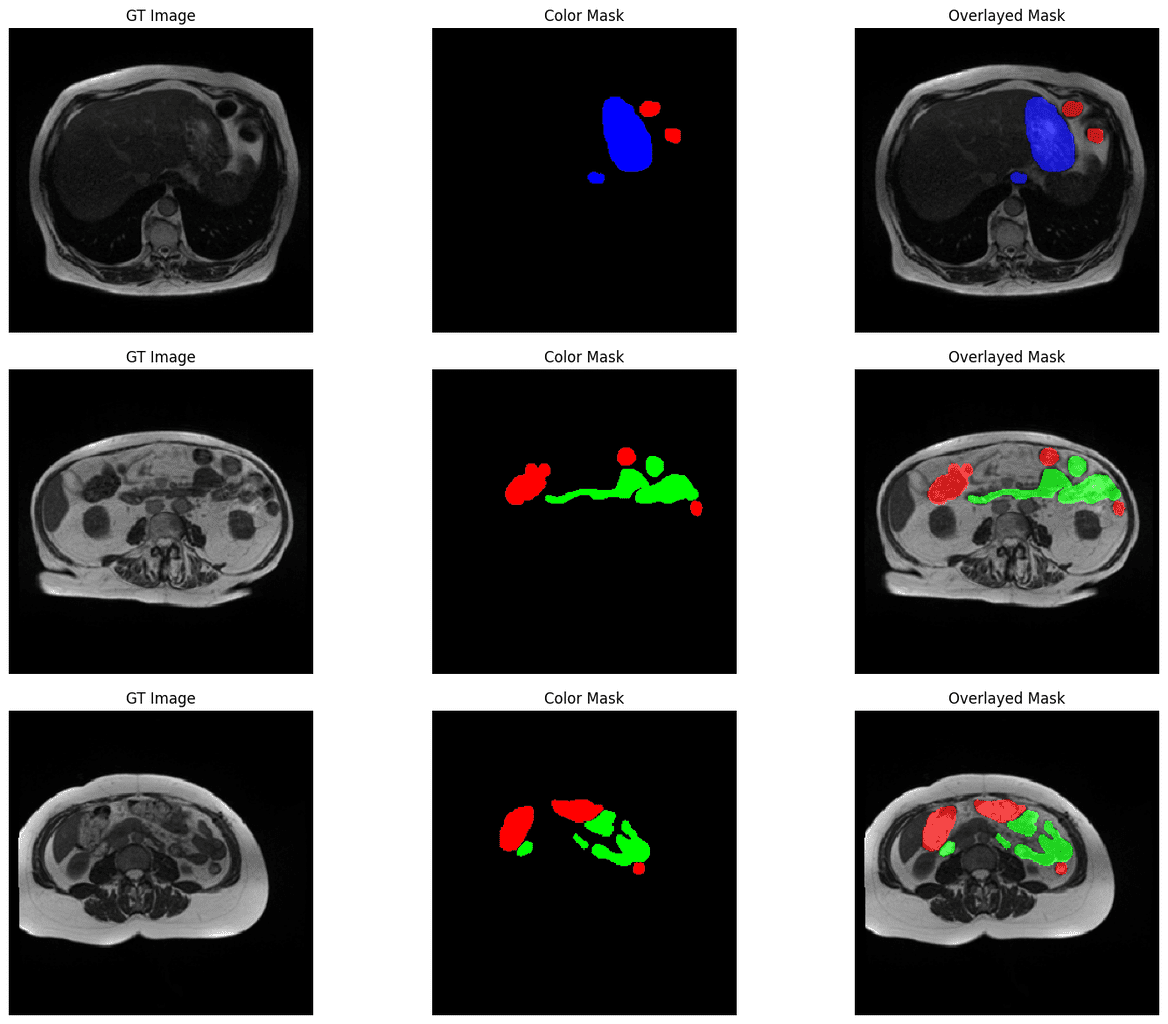

Medical Image Segmentation Using 🤗 HuggingFace & PyTorch Medical Image Segmentation Kaggle We organized the medical segmentation decathlon (msd)—a biomedical image analysis challenge, in which algorithms compete. With the result of different segmentation algorithm for evaluation purpose kaggle uses cookies from google to deliver and enhance the quality of its. Tips involve data analysis, training, model choice, and more. Dive deep into the challenging but incredible field of medical image segmentation! Explore. Medical Image Segmentation Kaggle.

Medical Image Segmentation Using 🤗 HuggingFace & PyTorch Medical Image Segmentation Kaggle Dive deep into the challenging but incredible field of medical image segmentation! The experiment set up for this network is very simple, we are going to use the publicly available data set from kaggle. Tips involve data analysis, training, model choice, and more. Automatic medical image segmentation plays a critical role in scientific research and medical care. Explore and run. Medical Image Segmentation Kaggle.